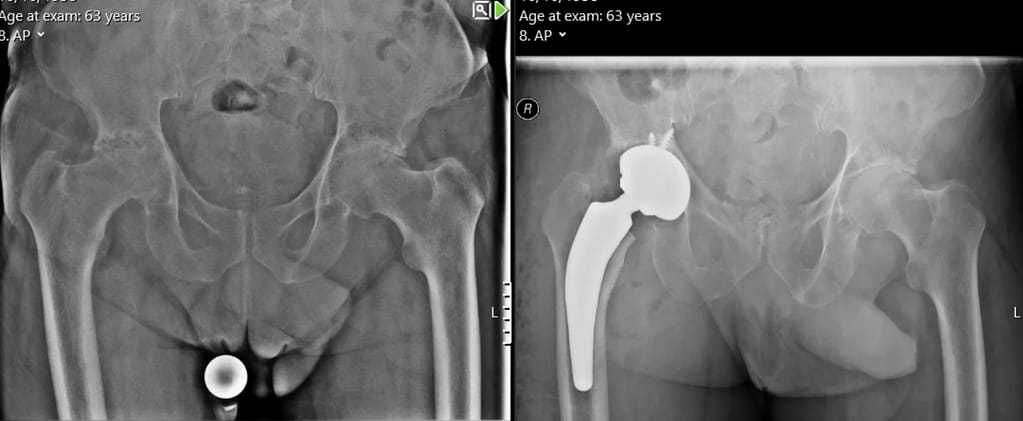

Mr MB is a 63-year-old man (see image above) with severe osteoarthritis of his right hip who underwent a right total hip replacement under the care of Mr Oragui from Grosvenor Orthopaedic Partners using a customised Symbios total hip replacement. Just a few weeks after surgery he is pain free in his right hip and mobilising independently without aides.